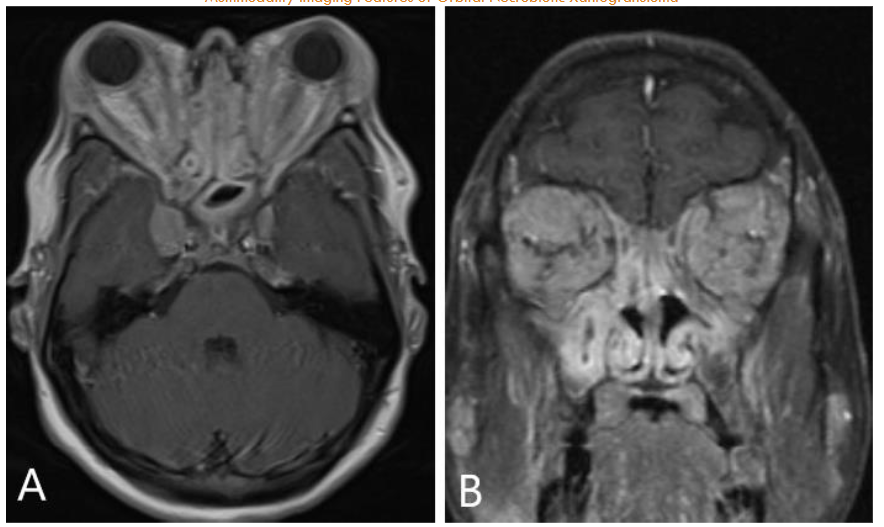

FDG PET/MRI was used to characterize the extent of the disease and determine the optimal site for tissue biopsy. FDG PET/MRI revealed multiple markedly FDG-avid cervical lymph nodes, focal intense uptake in the right parotid region, and focal uptake in the right orbital infiltrative mass with maximum Standardized Uptake Value (SUV) of 13. Guided by FDG PET/MRI, the patient underwent a biopsy of the most FDG-avid region of the right orbital mass, which was diagnosed as necrobiotic xanthogranuloma with increased IgG4 expression. The patient was treated with cyclophosphamide, corticosteroid, and high-dose IVIG followed by bone marrow stem cell transplantation and showed a good response in terms of both imaging and clinical evaluation. The genetic and histopathologic findings of this case are discussed in detail by Guess et al.